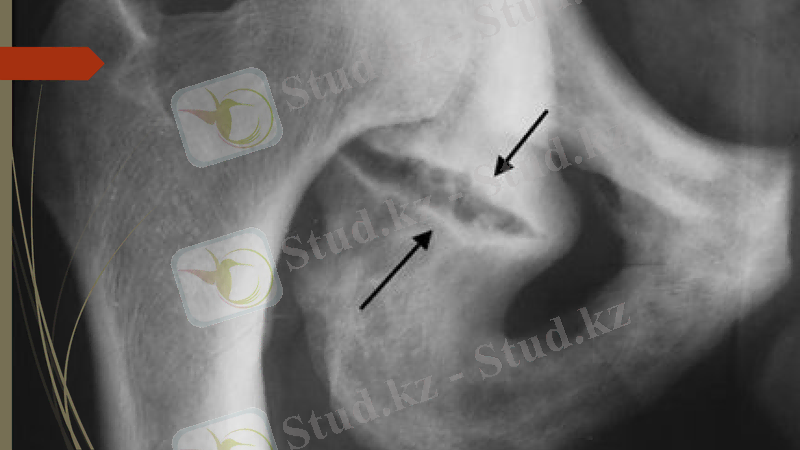

Рентген сәулесімен зерттеу әдісі - сүйек пен каңқаны зерттеп, диагноз қоюдағы ең жоғары сапалы эдіс болып табылады. Бүл әдістің тек сүйектін қүрылысын ғана емес, сондай-ақ сүйектену, сүйектің өсу динамикасын, тірек-қимыл системасының қимылдау кезеңіндегі ауруларын, сүйекті коршал түрған үлпалардың да ауруларын зерттеуде маңызы зор.

Осындай негізгі проекциялардан басқа, қосымша қиғаш проекция немесе жартылай қатпал сурет, мұнда ОСШ зерттелген объектіге қиғашынан бағытталады, мысалы алдынан жанына, ішкі жағына жэне артына.

Рентгенограмманы өзара перпендикулярлы екі проекцияда - т і к және ж а н ы н а н (немесе қ а п т а л), ал жануарлардың кейбір мүшелерін (бас қаңқасын, иық, асық буындарын) қиғаш проекцияда түсіру қажет